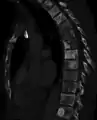

| Sclerosis of the bones of the pelvis due to prostate cancer metastases | |